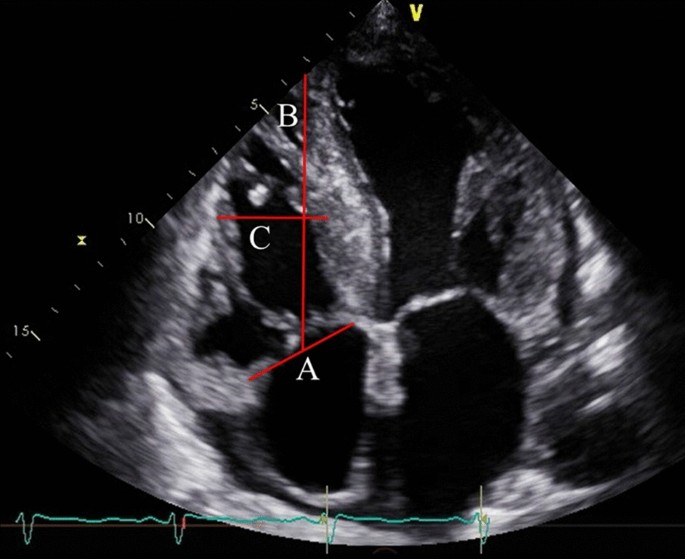

Echocardiography was conducted and analyzed by experienced cardiologists or clinical technologists. All patients underwent transthoracic echocardiography prior to TAVR. Severity of AS was determined based on the max velocity, mean pressure gradient, or AV area according to the ACC/AHA guideline3. LVEF, left ventricular end-diastolic volume (LVEDV), and left ventricular end-systolic volume (LVESV) were assessed by using modified Simpson’s biplane method. The right ventricular (RV) and atrial size and the diameter of the inferior vena cava were measured. RV sphericity index was calculated as the ratio between RV mid-ventricular and longitudinal diameters during the end-diastolic phase (Fig. 1)12, which is an indicator of RV remodeling13. LV sphericity index was also determined using same method as the RV sphericity index. Tricuspid annulus diameter was also measured during the end-diastolic phase. Systolic right ventricular function was assessed by TAPSE and RV fractional area change. Systolic pulmonary artery pressure (SPAP) was determined by measurement of the maximal tricuspid regurgitation velocity–derived gradient by continuous wave Doppler, inferior vena cava diameter, and respiratory-related changes in inferior vena cava diameter14. RV-PA coupling, which represents the association between the right ventricular contractility and pulmonary afterload, was defined as TAPSE-to-SPAP ratio (mm/mm Hg). Severity of mitral regurgitation (MR) and tricuspid regurgitation (TR) was scored on a scale ranging from 1 + (mild) to 4 + (severe)15 and 1 + (mild) to 5 + (torrential)16, respectively. None or trivial regurgitation was categorized as 0. MR and TR vena contracta (VC) were evaluated during the mid-systolic phase.

Definition of RV sphericity index. This echocardiographic image in apical four chamber view indicates measurement of RV sphericity index and tricuspid annular diameter. Initially, the tricuspid annulus diameter during the end-diastolic phase was measured (line A). Subsequently, a line was drawn connecting the RV apex to the midpoint of line A (line B). Finally, a perpendicular line was depicted connecting the RV free wall and septum, intersecting the midpoint of line B (line C). The RV sphericity index was calculated as the ratio between line C / line B. RV, right ventricular.